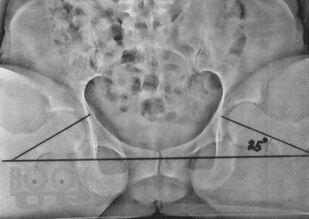

Учебное пособие содержит ценную информацию для врачей ортопедов и травматологов, занимающихся лечением повреждений и заболеваний проксимального отдела бедренной кости. В пособии представлена система рентгенологического и клинического обследования угловых величин - ан-теторсии, ретроторсии и шеечно-диафизарного угла - при планировании оперативных вмешательств по остеосинтезу переломов шейки бедренной кости и по эндопротезированию, исходя из индивидуальных форм кости каждого пациента. В работе описана методика определения длины канюлированных винтов и других фиксаторов для остеосинтеза шейки бедренной кости при еѐ переломах, используя анатомические и биомеханические параметры тазобедренного сустава исходя из здоровой стороны. Разработанная автором методика успешно использована при предоперационном планировании ургентного эндопротезирования и при повреждениях проксимального отдела бедренной кости.